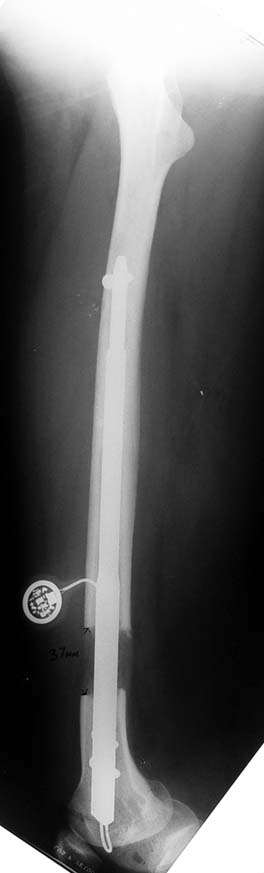

Vaka 1